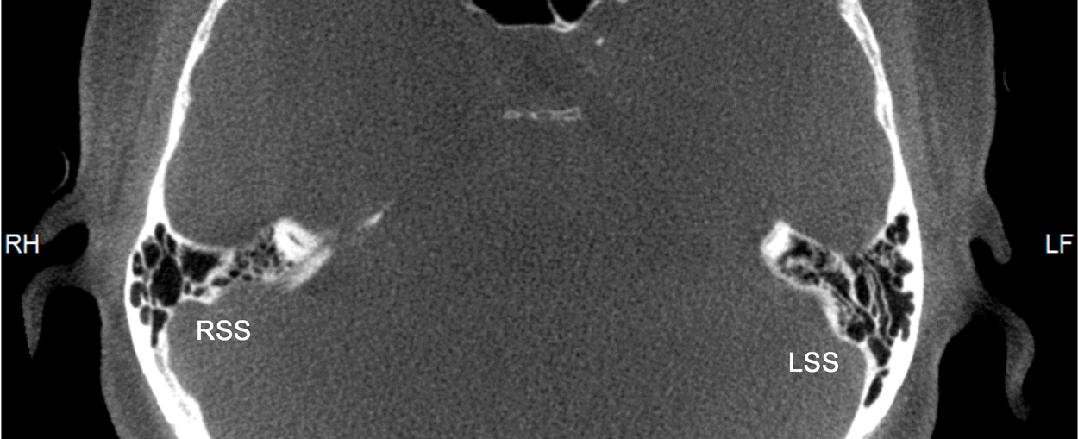

在颞骨CBCT(层厚0.2mm)上,我们发现该患者患侧(右侧)乙状窦骨壁有多个部位薄弱,而无颈静脉球高位。血管DSA排除了颅内血管病变、狭窄及颅内动静脉瘘。所以该患者的搏动性耳鸣大概率是因乙状窦引起。

颞骨CBCT显示的乙状窦骨壁局部薄弱(见箭头)乙状窦/颈静脉球相关的搏动性耳鸣发生机制尚不清楚,什么样的情况下会出现也很难解释。